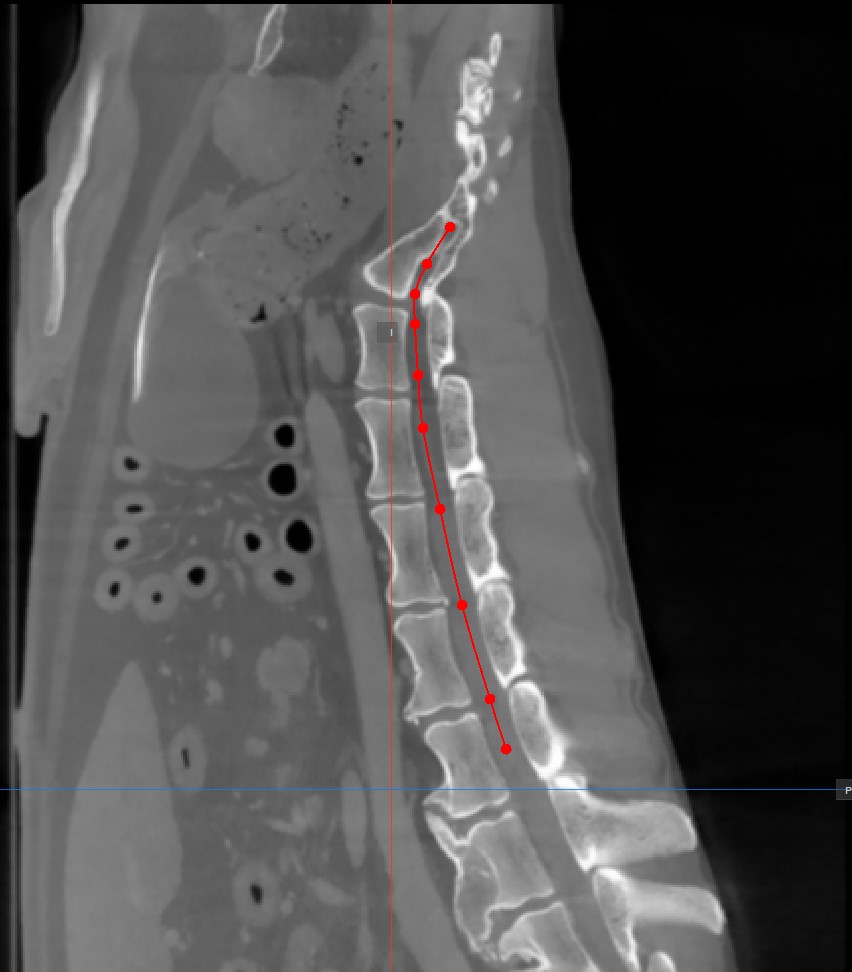

Curved MPR, eine Variante der MPR, erstellt Querschnittsbilder entlang eines vom Benutzer gezeichneten gekrümmten Pfades. CMPR kann besonders nützlich sein, um komplexe oder unregelmäßige Strukturen wie Blutgefäße oder verschiedene Wirbelsäulenstrukturen darzustellen.

Die Punkte, die den Pfad erzeugen, müssen in einem der drei verfügbaren Standard-MPR-Viewports auf der rechten Seite des Fensters platziert werden. Wählen Sie die am besten geeignete Ebene für die Anforderungen aus.

Mindestens zwei Punkte müssen auf den Bildern platziert werden, um den Pfad zu erzeugen. Die CMPR-Ansicht wird detaillierter, je mehr Punkte zum Zeichnen des Pfades verwendet werden.